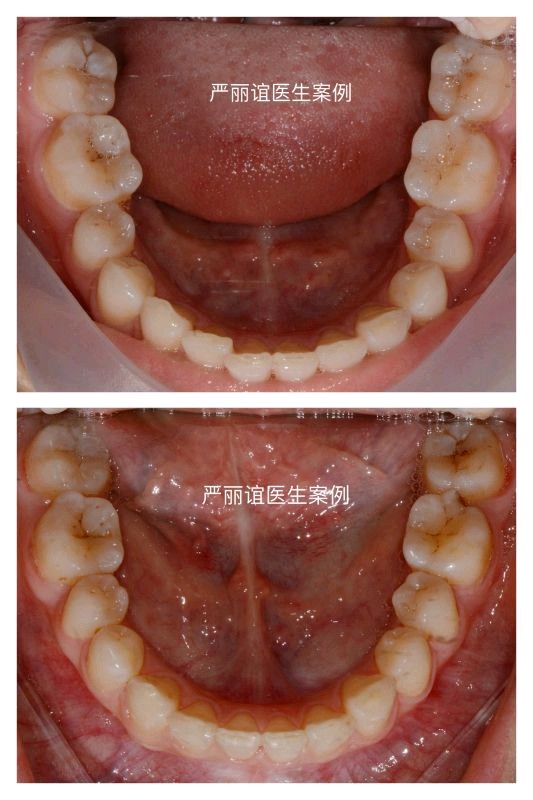

主诉:嘴凸,门牙有牙缝,前牙咬合深,要求矫正。

结果:双侧远中咬合关系,前牙深覆合深覆盖

矫正方案:拔除上颌两颗智齿,排齐整平上下颌牙齿,内收上颌前牙(种植钉辅助)改善侧貌,压低下颌前牙解除前牙深覆合,调整前牙到正常的覆合覆盖,后牙到中性咬合关系。